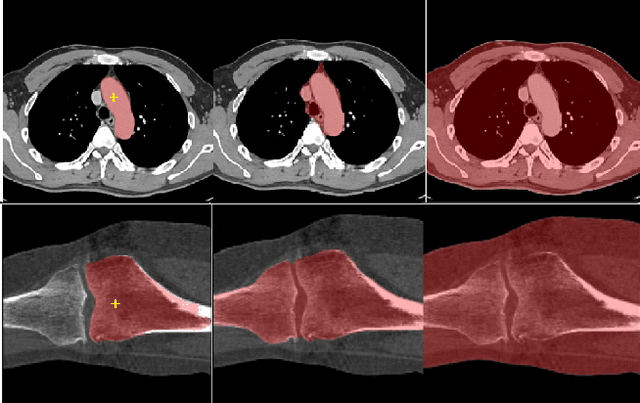

Abstract:We propose a straightforward yet highly effective few-shot fine-tuning strategy for adapting the Segment Anything (SAM) to anatomical segmentation tasks in medical images. Our novel approach revolves around reformulating the mask decoder within SAM, leveraging few-shot embeddings derived from a limited set of labeled images (few-shot collection) as prompts for querying anatomical objects captured in image embeddings. This innovative reformulation greatly reduces the need for time-consuming online user interactions for labeling volumetric images, such as exhaustively marking points and bounding boxes to provide prompts slice by slice. With our method, users can manually segment a few 2D slices offline, and the embeddings of these annotated image regions serve as effective prompts for online segmentation tasks. Our method prioritizes the efficiency of the fine-tuning process by exclusively training the mask decoder through caching mechanisms while keeping the image encoder frozen. Importantly, this approach is not limited to volumetric medical images, but can generically be applied to any 2D/3D segmentation task. To thoroughly evaluate our method, we conducted extensive validation on four datasets, covering six anatomical segmentation tasks across two modalities. Furthermore, we conducted a comparative analysis of different prompting options within SAM and the fully-supervised nnU-Net. The results demonstrate the superior performance of our method compared to SAM employing only point prompts (approximately 50% improvement in IoU) and performs on-par with fully supervised methods whilst reducing the requirement of labeled data by at least an order of magnitude.